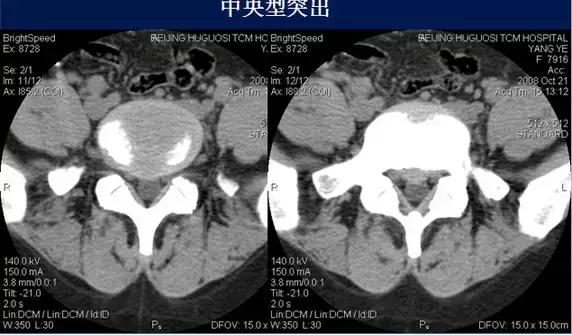

⑴中央型:椎间盘影局限性超出椎体边缘,硬膜囊可受压,硬膜外脂肪间隙变窄、消失,可伴纤维环钙化。